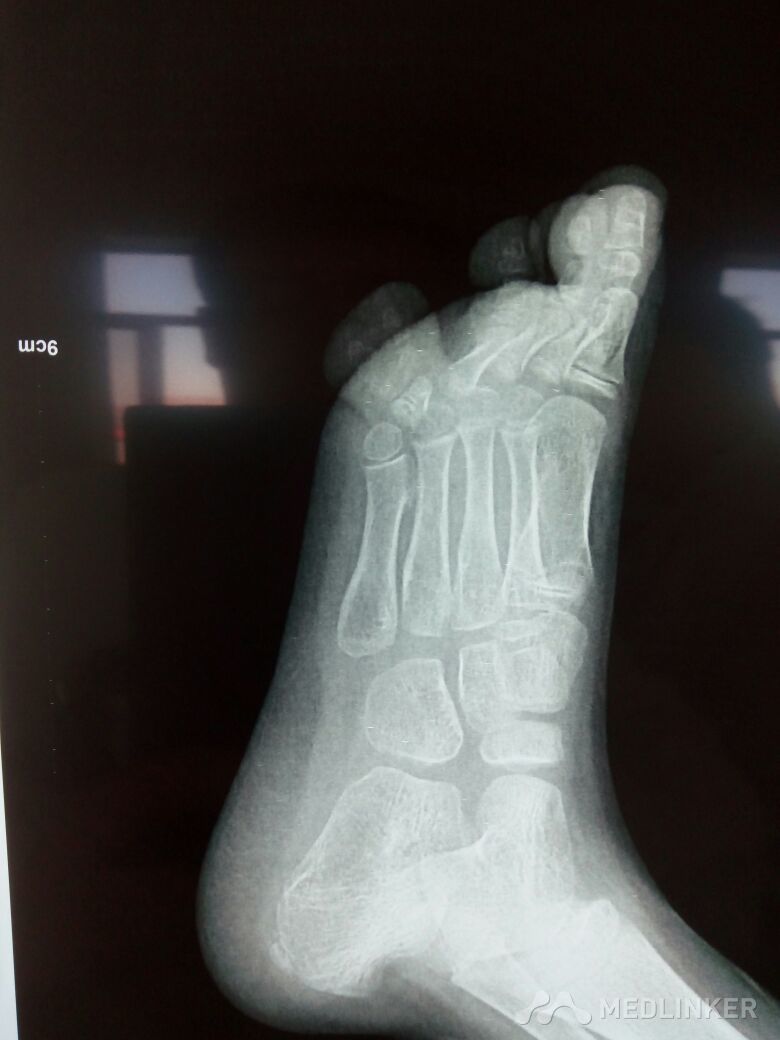

小儿多趾畸形一例

先天性足畸形

多趾畸形